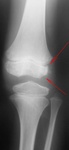

Мальчик 11 лет, жалобы на боли в коленных суставах в утреннее время. Движения в полном объеме, безболезненные, варусная деформация голеней с обеих сторон. У отца и деда выраженый гоноартроз.

Вопрос к детским рентгенологам (сама с детьми не работаю)-"лохматость" контуров суставных поверхностей бедренных костей у деток должна быть? А потом мне какие дополнительные тени кажутся, как суставные мыши у взрослых.

Патологии не вижу.

Костная структура соответствует возрастной норме. Единственное, что настораживает, великоват диастаз в межберцовом сочленинии. Я бы выполнила сравнительную рентгенографию обоих коленных суставов в прямой проекции с очень небольшой внутренней ротацией голеней 1 лучом на 1 пленке (с обязательным строгим соблюдением симметрии в укладке).

Но есть вопрос. А нормально ли "отстоит м/берцовая от б/берцовой?

Что стрелками помечено, так это нормально?

Костный возраст не соответствует 11 годам, по Садофьевой:

Полное окостенение эпифизов бедренной, большеберцовой и малоберцовой костей завершается несколько раньше (примерно в 8 лет)

Головки малоберцовок - как-то высоковато стоят по прямым снимкам, то ли укладка такая.

Вот-вот, и я об этом же. Дополнительные тени и нечеткость контуров.

Согласна, суставы не соответствуют возрасту, дополнительные тени - это добавочные ядра окостенения. Малоберцовые кости какие то длинные, щели межберцовых суставов широкие (в норме малоберцовая кость накладывается на большеберцовую). Вообщем, какие то диспластичные суставы. Костно-травматических изменений нет.

Мне периостальная реакция мерещится.

Согласен, но что-то ему болит. Скорее не рентгенологические проблемы, большая часть болей связана не с костной патологией.

Как правило, если имеют место "утренние боли", а если ещё и утренняя скованность, то нужно исключать различного рода артриты. Плюс ко всему нужно помнить о "болях роста". Варусная деформация с болями никак не связана, у детей вообще крайне редко любые деформации болят.

подозрение здесь на 2сторонний рассекающий остеохондрит ,ко-ый может иметь место в 30% случаев .слева в проекции дистального эпифиза бедра ,в проекции латерального мышелка бедра ,определяются точки окостенения ,один из находится на большом удалении от мышелка,чего не должно быть ,вероятнее всего яв-ся костным фрагментом.справа четко определятся костный фрагмент вогнутой формы (ядро окостенения всегда должно быть в этой зоне округлой формы ),с нечеткостью замыкательной пластинки (размытость).решить вопрос может мрт-будет отек и гипоинтенсивный сигнал во всех последовательностях(участок некроза)

Всё то, что Валентин Львович отметил стрелочками - не норма. Я бы описал на месте автора побробно снимок без заключения, а остальное предоставил ортопеду. У нас так и делается. И это правильно.